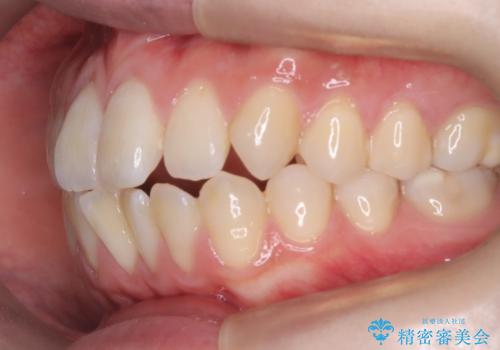

【ワイヤー矯正】前歯の突出感、下の歯の並びを良くしたい

- 主訴:上の前歯の突出感と下の歯の並びを改善したい

非抜歯で矯正治療を行った場合と、上下左右4番目の歯を抜歯して矯正治療を行った場合のシミュレーションを見ていただき、非抜歯での矯正治療を希望されました。

非抜歯にて矯正治療を行いました。

IPRを行い、前歯部の突出感の改善に努めました。

期間:1年9カ月